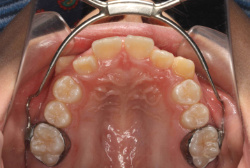

混合歯列期から治療開始した側方拡大による非抜歯症例

「配列の凸凹を治したい」という主訴で来院したケースです。診断の結果、永久歯がすべて生えそろうと、かなり厳しい叢生(歯並びの凸凹のことです)になる可能性が高いと判明しました。原因としては特に上の顎の骨が小さいため、歯を収容する容量不足になっていると診断しました。このケースの場合は、成長発育期に治療開始しますので、顎の骨を土台ごと大きくすることが可能です。

そこで、まず急速拡大装置を使用して上顎骨の拡大を行い、上顎骨の容量が拡大したことを確認後、マルチブラケット装置を使って全体の修正をする、と言う二段階の作戦をとることになりました。

この時期に使う急速拡大装置は、適切な診断に基づいて正しく使用することで確実に骨を大きくすることができます。拡大することで隙間が確保できるので、永久歯の抜歯を避けることができます。

急速拡大装置を1日1回装置の中央にある拡大ネジを、ご自身で回して頂くことで25日間くらいかけて、6mmほど拡大しました。拡大後は、上顎の前歯の隙間が広がっていることがお分かりいただけると思うのですが、土台の骨ごと広がるのでこのような隙間ができます。その後1年半くらいマルチブラケット装置を使用して、全体の修正を行いました。

結局、歯の本数を減らすことなく、すべてご自分の歯を残して正しい配列にすることができました。このケースの場合、2009年10月より拡大と経過観察を行い、2012年3月より1年2ヶ月マルチブラケット装置を装着、2013年5月に治療を終了しました。2段階で行う治療としては短期間で終了しているケースと思います。